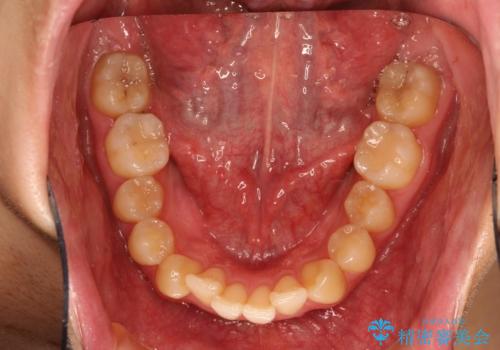

- 前歯の凸凹を主訴に来院された患者様です。

インビザラインにて治療を行いました。